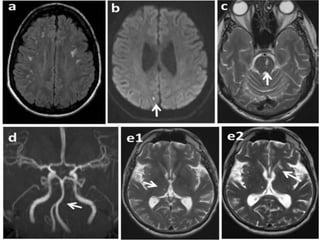

a) CNS

i. lesions affect white and gray matter and are

more frequent in the posterior circulation

ii. vessel ectasia frequent in the posterior

circulation

iii. chronic findings might be detected in

magnetic resonance imaging

iv. MRI, characterized by progressive white-

matter lesions, which occur early in the

course of FD

a) CNS i. lesionsaffect white and gray matter and are more frequent in the posterior circulation ii. vessel ectasia frequent in the posterior circulation iii. chronic findings might be detected in magnetic resonance imaging iv. MRI, characterized by progressive white- matter lesions, which occur early in the course of FD